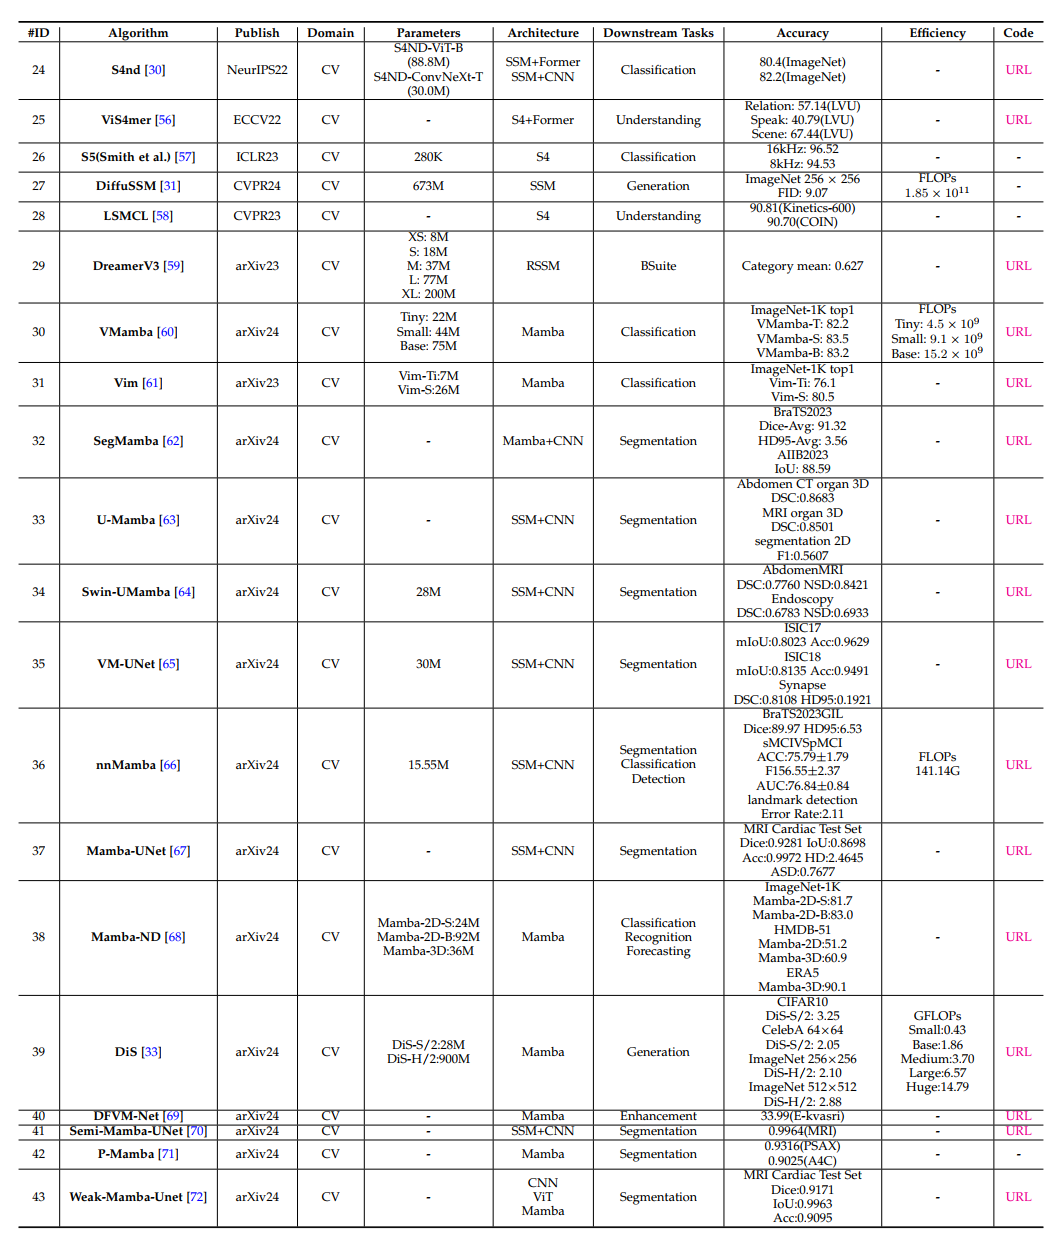

3)计算机视觉(Computer Vision)

分类(classification)

检测(detection)

分割(segmentation)

医学(medical)

重构(restoration)

生成(generation)

视频理解(video understanding)

跟踪(track)

其它(other)